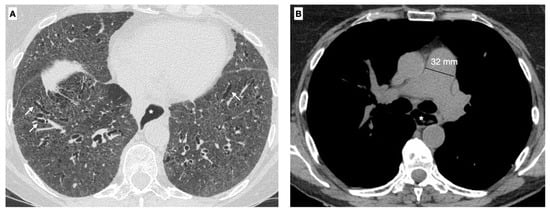

- Ruaro, B.; Baratella, E.; Confalonieri, P.; Confalonieri, M.; Vassallo, F.G.; Wade, B.; Geri, P.; Pozzan, R.; Caforio, G.; Marrocchio, C.; et al. High-Resolution Computed Tomography and Lung Ultrasound in Patients with Systemic Sclerosis: Which One to Choose? Diagnostics 2021, 11, 2293. [Google Scholar] [CrossRef]

- Bruni, C.; Mattolini, L.; Tofani, L.; Gargani, L.; Landini, N.; Roma, N.; Lepri, G.; Orlandi, M.; Guiducci, S.; Bellando-Randone, S.; et al. Lung Ultrasound B-Lines in the Evaluation of the Extent of Interstitial Lung Disease in Systemic Sclerosis. Diagnostics 2022, 12, 1696. [Google Scholar] [CrossRef]